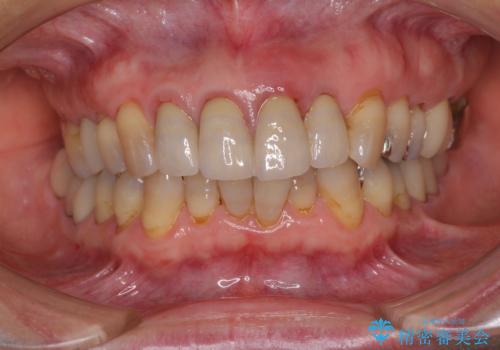

3. 折れてしまった前歯 インプラントによる補綴治療の治療後

1. 折れてしまった前歯 インプラントによる補綴治療の治療前